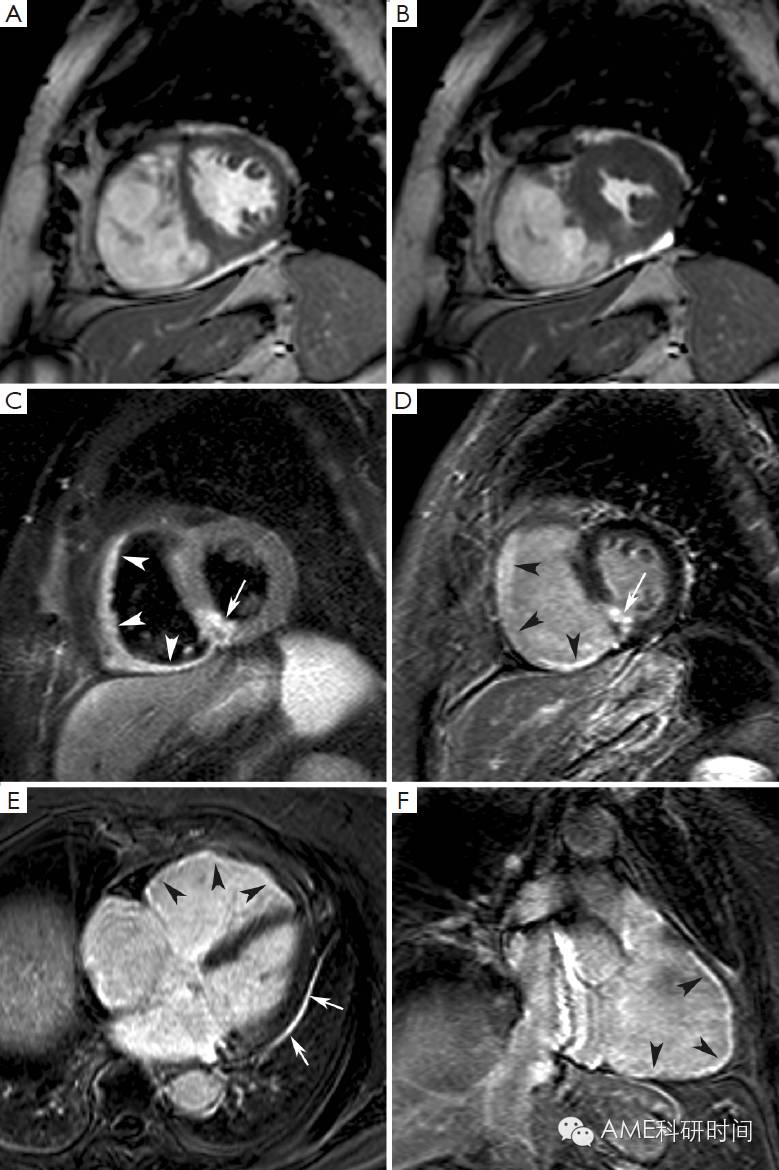

在过去的几年里,越来越多的证据表明,通过短时间反转回复序列(STIR) T2加权像的影像数值,可以判断危险心肌,即在冠状动脉阻塞时可通过再灌注得到挽救的心肌(2)。事实上,T2加权像STIR对组织游离水(水肿)的增加特别敏感,而游离水的增加通常伴随缺血性心肌损伤,无论组织是否坏死(3,4)。心肌水肿(缺血引起ATP依赖的钠钾离子通道的功能紊乱,导致膜两侧钠离子梯度的改变,从而引发细胞内水肿)是缺血性损伤的早期症状,T2加权像STIR成像对于在急诊中患有不稳定型心绞痛和不断发展的心肌梗死患者是一种非常有用的诊断手段(5,6)。尤其是在T2加权像STIR影像中,心肌水肿会呈现出强烈信号(亮)(见图1)。Abdel-Aty等人(7)的最近研究显示,通过水肿造影描绘了在缺血发生后30分钟内及不可逆性心肌损伤[表现为肌钙蛋白水平增高和迟发钆增强(LGE)]前急性心肌损伤的情况。Aletras等人(2)用实验证明了在发生再灌注心肌梗死两天后的T2加权像STIR影像中,水肿的面积对应于在发生冠状动脉阻塞时微球注射所呈现的危险心肌的面积(即参考标准)。此外,危险心肌面积明显大于最终发生梗死的心肌面积,说明在T2加权像STIR影像中呈现的水肿区域同时包括了可逆和不可逆损伤的心肌(即永久性心肌损伤)。最近在再灌注后ST-段抬高的心肌损伤患者中,使用单光子发射计算机断层成像术(SPECT)对这项技术进行检验。在急性心肌梗死7天后,使用经皮冠状动脉介入治疗前,通过99mTc-替曲膦SPECT看到的灌注不足区域与通过T2加权像STIR影像检测到的心肌水肿区域相似(8)。因此,T2加权像STIR成像术能够在不干扰急性期患者诊治的情况下,对危险心肌组织进行准确的、可回顾的和非电离的检测。此外,在急性再灌注心肌梗死的病人中,我们和其他一些研究组证明此技术得到的结果和血管造影术对危险心肌评分结果的一致性(9,10)。然而,最近有人对T2加权像STIR成像描绘危险心肌组织的准确性产生怀疑,因为它具有对人造品固有的高灵敏度和可重复性差(11)。此外,此技术的操作序列导致信噪比低及易于在心内膜和心室腔的边界检测到“血流慢”的假象。重要的是,我们对T2加权像STIR成像所确定的危险心肌组织的认识来源于数量相对较少的试验研究,需要进一步的研究。在这种情况下,产生了更好的序列产生了,例如T2加权稳定态自由旋进造影或T2弛豫时间图(12,13)。众所周知,T2加权异常在急性和亚急性预后阶段表现最明显,但是随梗死诱发的心肌水肿和炎症的再吸收而慢慢退去(8)。因此,T2加权STIR的序列能够将急性和慢性心肌梗死区分开来(14),因为在T2加权STIR成像中前者伴随着心肌水肿,而后者没有显现水肿。最后一点,T2加权STIR成像能够显现再灌注后心肌出血情况。事实确实如此,无再灌注的心肌梗死,一般不会导致出血,而再灌注的梗死不同与此,经常出现由缺血性再灌注引起的严重微血管损伤,从而导致明显的红细胞渗出(15)。活体和尸检研究显示通过检测血红蛋白降解物的顺磁性,T2加权具有辨别心肌内出血的能力,这将缩短T2弛豫的时间(16,17)。因此,水肿的图像显示出血性梗死区域的不均一性,通常呈现低亮度的核心和高亮度的边缘,因此可与非出血性梗死区别开来,因为非出血性梗死呈现亮度均匀的心肌(图2)。对98位患有再灌注ST段抬高的心肌梗死患者研究,发现25%的患者心肌内出血(18)。这些出血性梗死的患者出现更大的梗死面积和透壁性心梗,更大的无复流区和更少的心肌复活。心肌内出血,是独立于初始梗死面积,不利于左心室重塑的因素。之后,Eitel等人(19)研究发现T2加权检测出心肌出血,预测心肌梗死后6个月发生重大心血管疾病。

图1 Edema imaging in a patient with a reperfused acute anteroseptal myocardial infarction (day 3 post MI). Short-axis T2-weighted STIR imaging at 4 levels (A-D). The jeopardized, edematous myocardium is visible as the myocardium showing increased signal intensity (arrowheads, A-C). Note the extension of the edema towards the adjacent RV anterior wall (arrows, A-D). Adapted from Ischemic Heart Disease by Bogaert J and Dymarkowski S, in Clinical Cardiac MRI Second Edition, Bogaert J, Dymarkowski S, Taylor AM, Muthurangu V (eds). Springer Heidelberg, Germany (ISBN 978-3-642-23034-9).